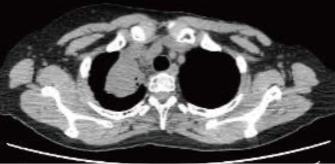

一次化学療法開始前(2018/12)

縦隔腫瘍に圧迫され気管と大動脈弓が変位